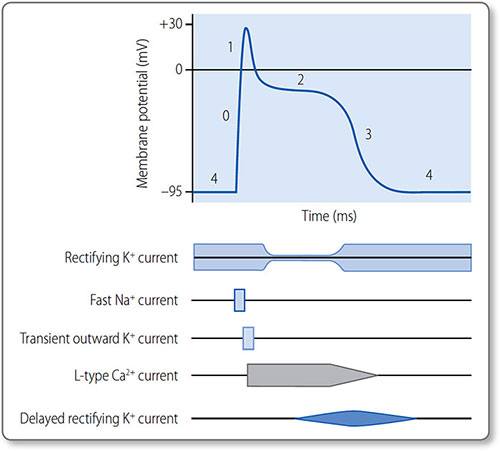

The cardiomyocyte action potential has five phases (0–4) controlled by ion channel activation and inactivation (Figure 1.22). Phase 4 corresponds to diastole and phases 1 and 2 to systole.

Phase 4: resting

The membrane is permeable to K+ and relatively impermeable to other ions. Cardiomyocytes are held at RMP, polarized between –90 and –95 mV.

Figure 1.22: The cardiac action potential and the activation and inactivation of gated ion channels. The phases are 0, depolarization; 1, transient partial repolarization; 2, plateau; 3, repolarization; and 4, resting.

33Phase 4 ends when a depolarizing electrical stimulus is conducted to the myocyte from a neighbouring cell. If it increases the membrane potential to –60 mV, an action potential (phase 0) is triggered.

Phase 0: depolarization

The threshold potential activates voltage-gated fast Na+ channels and Na+ ions rush into the cell, down a steep concentration gradient. INa rapidly increases the membrane potential to around +30 mV, when fast Na+ channels abruptly inactivate.

Phase 1: transient partial repolarization

Voltage-gated, transient outward K+ channels activate to allow a brief efflux of K+ (Ito). This causes a brief partial repolarization.

Phase 2: plateau

Voltage-gated L-type Ca2+ channels activate and inactivate slowly, which prolongs inward Ca2+ current (ICa); this sustains the action potential for around 250 ms and triggers myocyte contraction.

Toward the end of phase 2, Na+–Ca2+ exchangers allow slow entry of Na+, extending the plateau phase.

Ca2+ and Na+ influx is opposed by outward rectifying K+ currents.

Phase 3: repolarization

As the L-type Ca2+ channels inactivate, delayed rectifying K+ channels open. The now unopposed K+ efflux causes rapid repolarization.